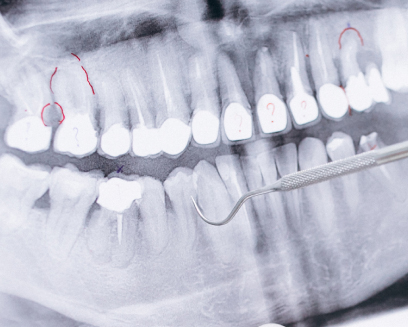

Root canal treatment at Nebras Medical Center in Ras Al Khaimah

is needed when the tooth’s pulp becomes infected or damaged.

This can occur due to severe decay, deep cavities, repeated dental

procedures on the tooth, or trauma.